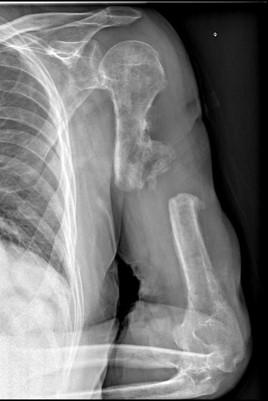

Fracture de l’extrémité supérieure de l’humérus